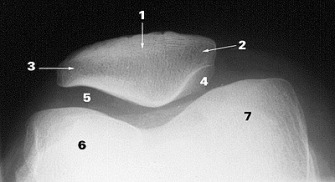

The patella is apically shaped and it`s undersurface, or articular surface, is coated with thick hyaline cartilage to reduce friction as it glides over the distal femoral condyles, also coated with cartilage. When you disarticulate a chicken leg, the white “shiny” surfaces of that joint complex is articular cartilage.

The “retro patellar” (under) surface has a central prominence or ridge, designed to “track” within the central groove created by the two femoral condyles (6 and 7). The patellar under surface is also divided into 4 articular “facets” (medial 4, lateral 3, central, odd 2). Each facet has a range of motion dictated role in absorbing compressive loads as it operates as a pulley. The lateral facet absorbs load in extension of the knee, and correspondingly the medial and odd facets during flexion.  Compressive loads between the femur and patella can be enormous, often hundreds of pounds (Cohen et al, Amer J Sports Med, 29 (4), 2001 and Powers et al, J Ortho Sports Phys Ther, 44, 2014).  To accommodate these loads, the “retro-patellar” articular cartilage is the thickest in the body, approaching 7mm along the central ridge (Ahmed et al, J Orthop Res, 1987). Despite the durability of the patella, surface lesions do occur and unfortunately the hypo- vascular nature of articular cartilage restricts healing once damaged.